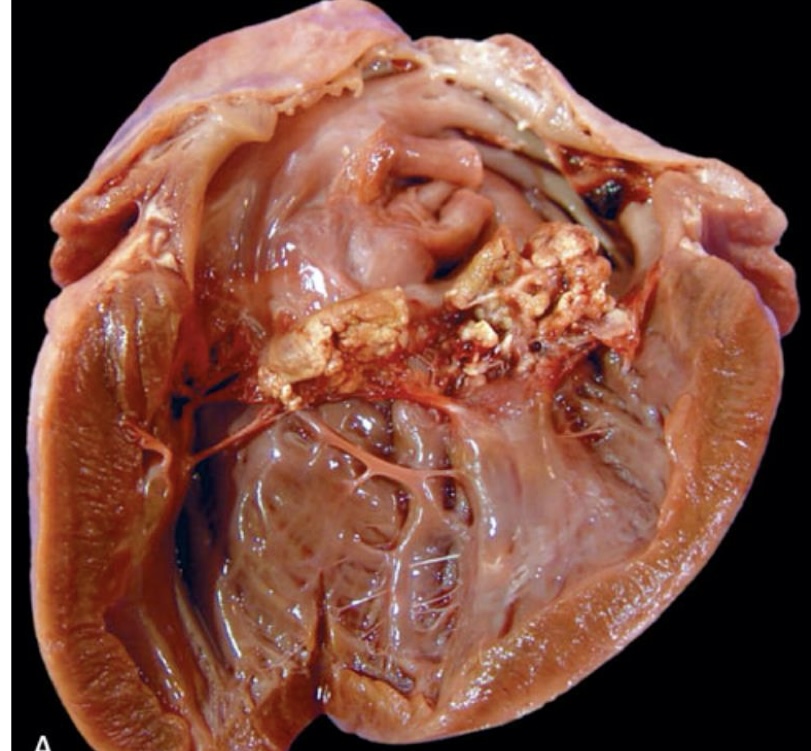

what is this?

vegetative valvular endocarditis → friable yellow material adhering to left AV valve